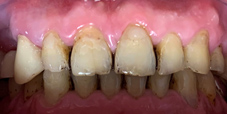

噴砂美白及居家美白前

噴砂美白及居家美白後